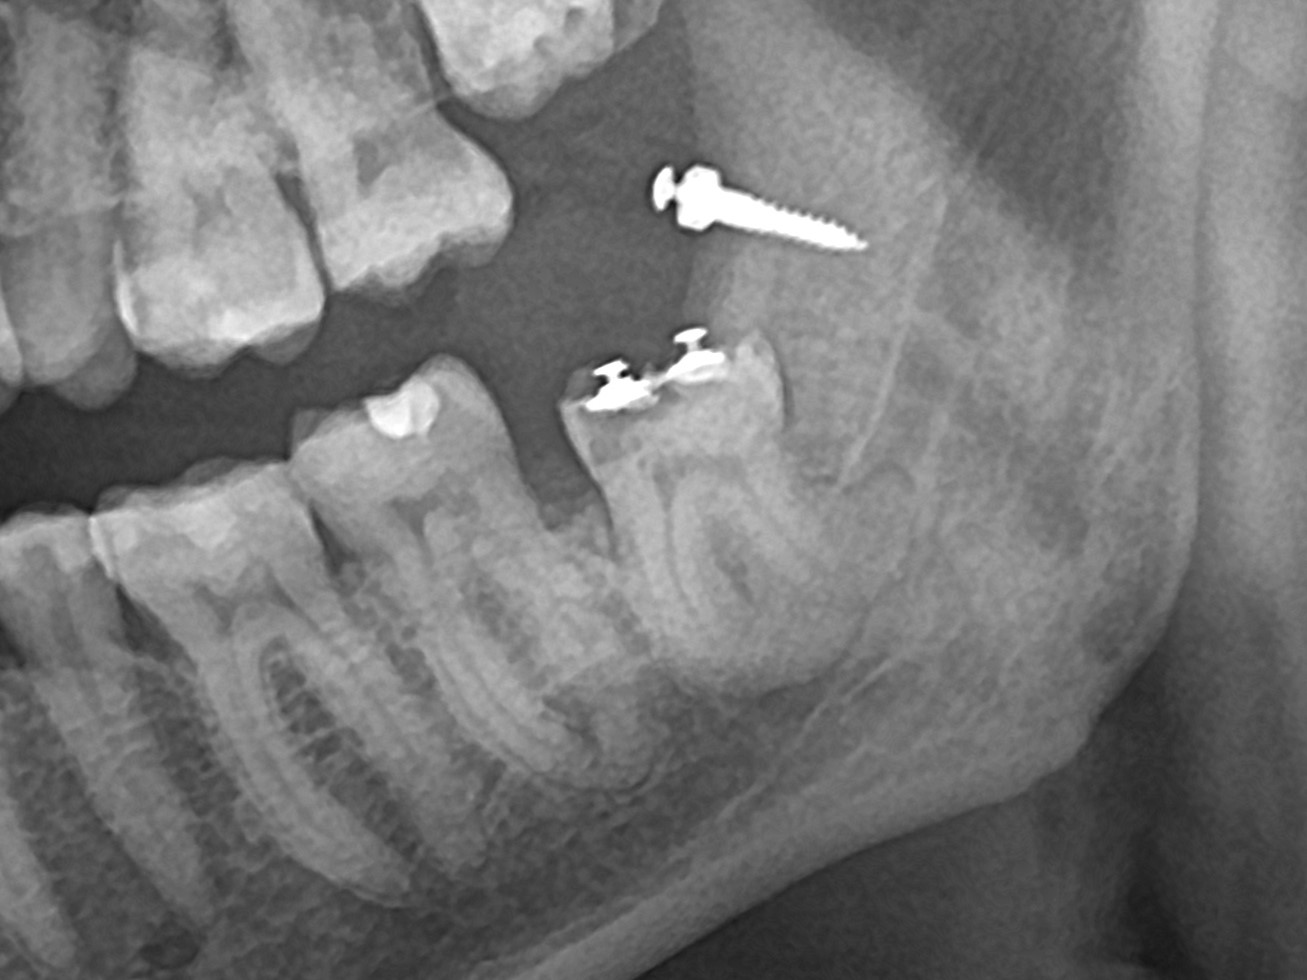

диагностическая ОПТГ

послеоперационная ОПТГ